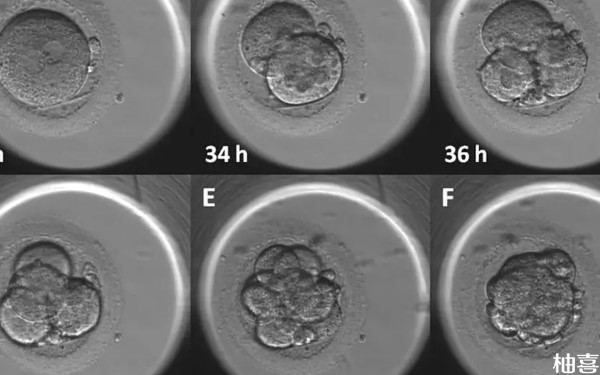

促排卵针打了后多久打夜针?

不孕不育症女性患者一般在使用促排卵药物8-12天后打夜针,夜针通常为肌肉注射或皮下注射药物,需要来诊用药;一般注射夜针后34-36小时后取卵。而在此期间,为保证卵泡的正常发育,建议在饮食上尽量多以清淡饮食为主,不要进食辛辣刺激性食物。另外需保证充足睡眠,精神放松不要过于紧张。